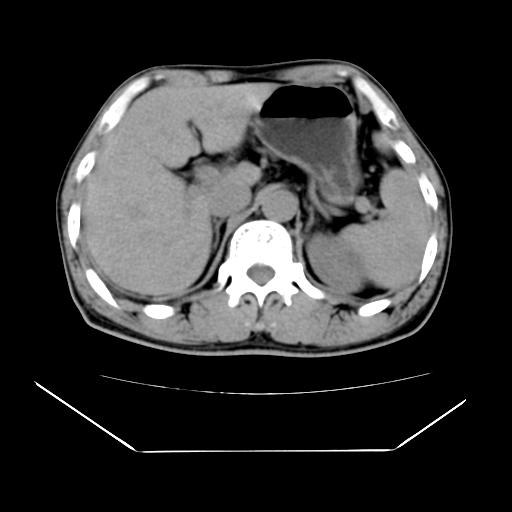

男性,55岁,外院体检afp明显升高,但b超未发现异常,否认乙肝病史。来我院ct增强。有延时扫描。

肝脏右叶动脉期可见低密度影,至延迟期被充填,考虑血管瘤可能性大。

肝右叶病灶

不排除肝右叶肝癌可能。

如果这个是癌灶的话则下腔静脉有瘤栓可能

肝6段血管瘤

血管瘤可能性大。

考虑肝右静脉影。